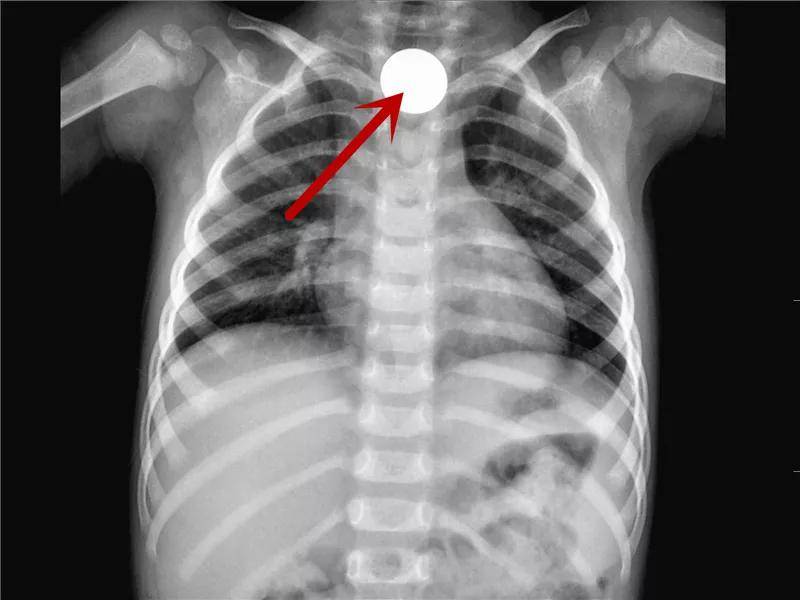

硬币的一场“旅行”

硬币是儿童消化道异物中最最最常见的。虽然有些孩子可以自行排出,但是部分幼龄患儿仍需手术取出。家长还是当心点吧!

进入食道上段